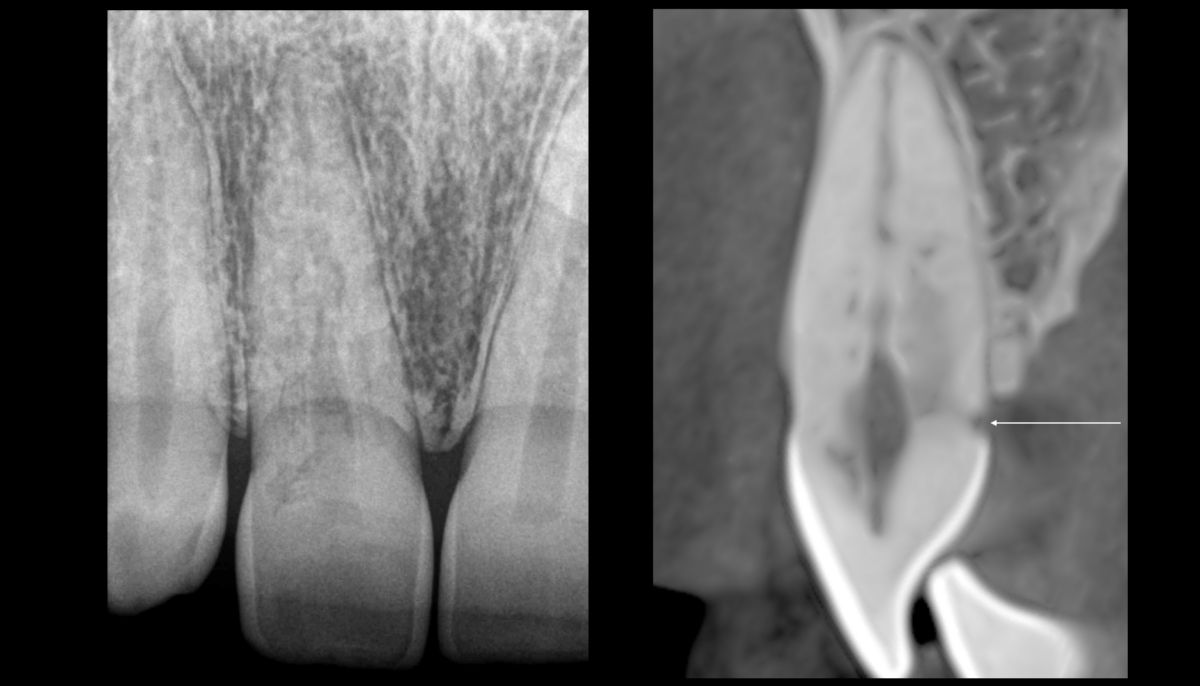

🔬 Lorsque la résorption est initiée dans le cément, on distingue 2 modèles histologiques :

🧬 𝐔𝐧 𝐭𝐢𝐬𝐬𝐮 𝐜𝐨𝐧𝐣𝐨𝐧𝐜𝐭𝐢𝐟 𝐚𝐯𝐞𝐜 𝐮𝐧 𝐢𝐧𝐟𝐢𝐥𝐭𝐫𝐚𝐭 𝐥𝐲𝐦𝐩𝐡𝐨𝐩𝐥𝐚𝐬𝐦𝐨𝐜𝐲𝐭𝐚𝐢𝐫𝐞 𝐝𝐞𝐧𝐬𝐞 (tissu de granulation), souvent recouvert par un tissu épithélial.

🦴 𝐔𝐧𝐞 𝐜𝐫𝐨𝐢𝐬𝐬𝐚𝐧𝐜𝐞 𝐝𝐞 𝐭𝐢𝐬𝐬𝐮 𝐫𝐞́𝐩𝐚𝐫𝐚𝐭𝐞𝐮𝐫 𝐫𝐞𝐬𝐬𝐞𝐦𝐛𝐥𝐚𝐧𝐭 𝐚̀ 𝐝𝐮 𝐭𝐢𝐬𝐬𝐮 𝐨𝐬𝐬𝐞𝐮𝐱 (bone-like tissue)